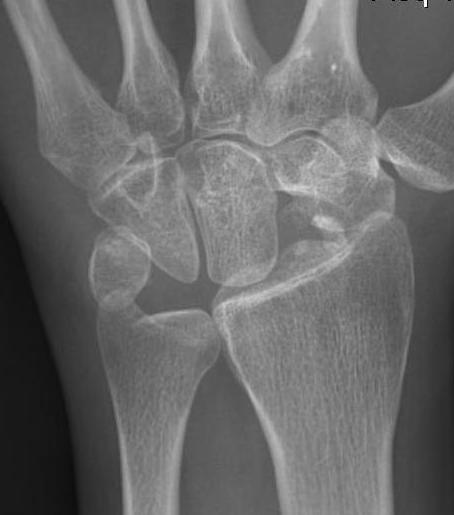

| Stage II | Stage IIIA |

|---|---|

| Sclerosis |

Collapse / fragmentation Normal carpal height |

![]() |